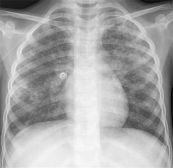

Hẹp động mạch phổi là khuyết tật tim bẩm sinh, khi đó van động mạch phối cho phép máu ra khỏi tim đến phổi của trẻ, có cấu tạo không bình thường. Vậy nguyên nhân và triệu chứng của bệnh là gì? Làm thế nào để điều trị và phòng ngừa bệnh hiệu quả? Tham khảo bài viết dưới đây để hiểu rõ hơn nhé!